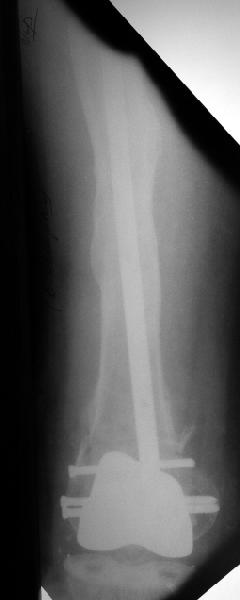

В итоге сделали антеградный остеосинтез. В дистракторе свежий перелом вправился сразу, а вот старый - оставил проблему, дистальный отлмомк остался все равно кзади. И гвоздь бы прошел кпереди от него, а ретроградный - перфорировал бы передний кортекс. Так что пришлось еще сделать чрескожную остеотомию через перелом, чтобы малость мобилизовать дистальный отломок. Снимки в прилжении.

The radiographs look excellent and a good outcome would be anticipated. The idea to osteotomize the femur shaft to compensate for the prior shaft malunion was clever and should work fine.

I can't actually see the osteotomy on either radiograph. Is it more proximal than we see in these radiographs or so well aligned as to be not visible?

The osteotomy was perfromed trough the fracture site. See the image.